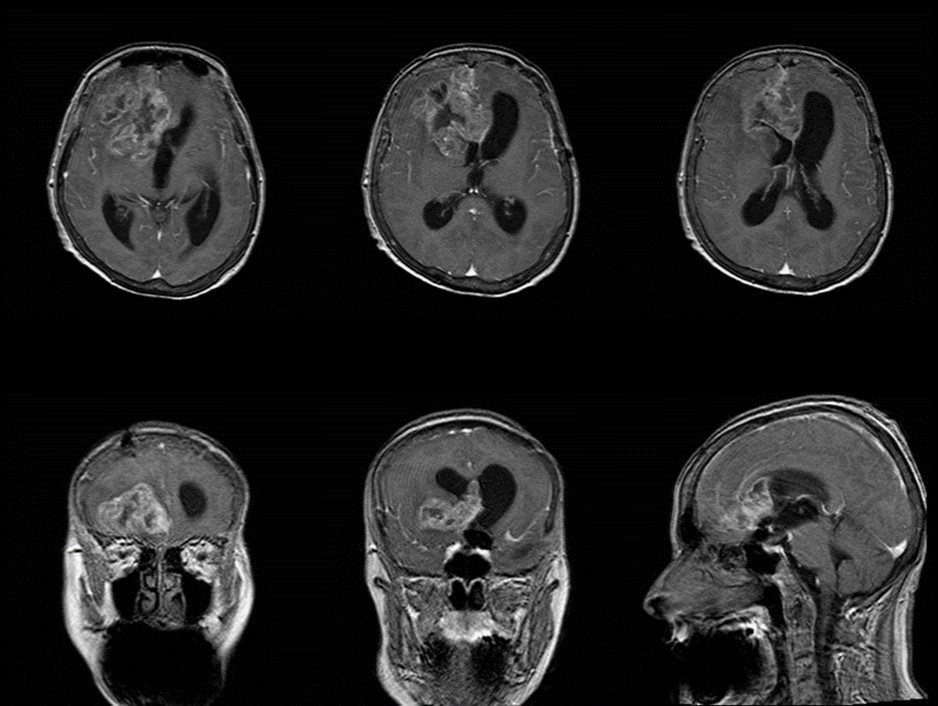

The follow-up CT scan made two weeks later showed a mild ventricular enlargement and persistent density alterations in the frontal region (Figure 2) that were interpreted as normal. Once discharged at home, the patient developed progressive disorientation that finally let her refer to our hospital for consult four months after aneurysm clipping. The cerebral CT we performed showed further ventricular growth, and a tumor-like image in the right frontal lobe (Figure 3). She was admitted to our ward and underwent a contrast-MRI that confirmed the suspicion of aggressive intra-axial neoplasm (Figure 4). The week after, under general anesthesia we performed a right craniotomy and removed a large part of the tumor, sparing the portion going through the corpus callosum (Figure 5). During convalescence the patient had few epileptic attacks, treated with drugs. A mild cognitive impairment persisted after surgery, without focal motor deficits. The gait, limited and unstable since the SAH, remained poor and the patient never walked again after the operation. The histological examination indicated a WHO grade IV glioma: IDH1-p53 negative glioblastoma. The patient and her relatives refused a ventriculo-peritoneal shunt after knowing this unfortunate diagnosis. Transferred to rehabilitation, the woman made just a short low-dose chemotherapy cycle and finally died four months after tumor resection.

Figure 4.Pre-operative contrast axial, coronal and sagittal MRI. Glioma of the right frontal lobe, extending contralaterally